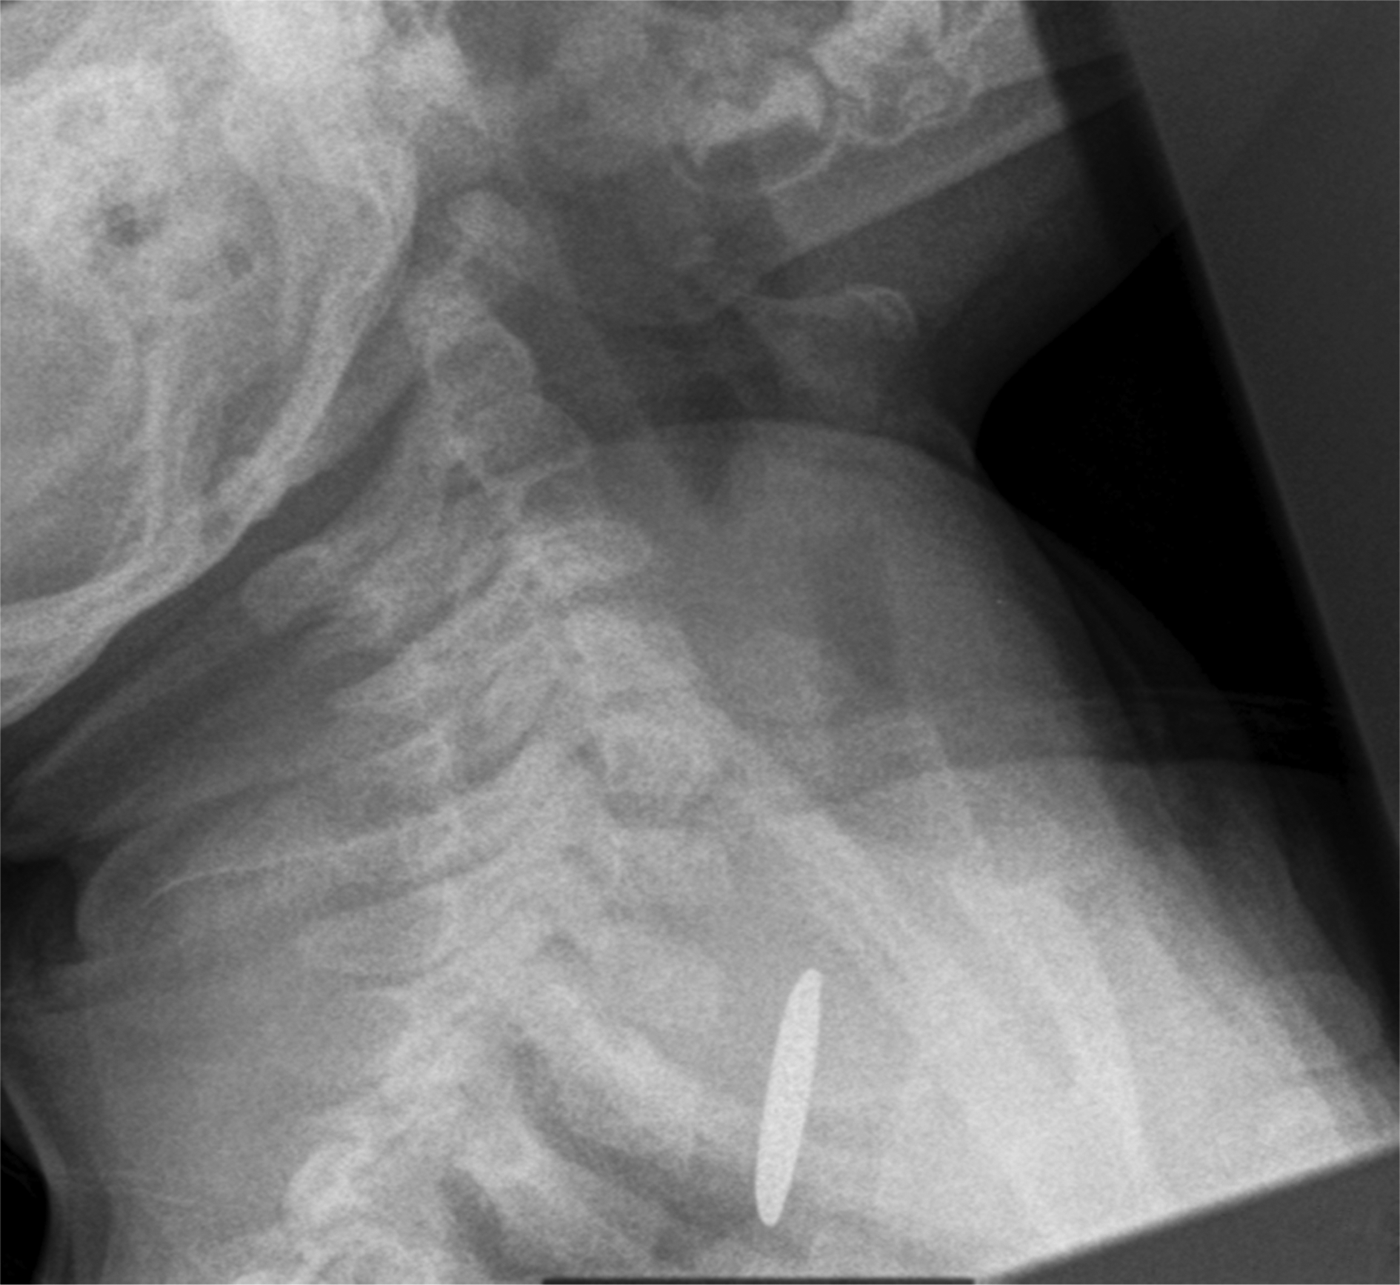

The button battery ingested by the patient. These battery changes Accidental Button Battery Ingestion If the patient is ≤ 12 years, immediately obtain. In recent years, particular dangers, specifically from ingested button batteries, have become increasingly recognized as a public. Note extent, depth and location of tissue damage, and. He was vomiting when admitted. Button batteries (bb) are found in common household items and can lead to. Endoscopic removal is recommended as allows direct. Accidental Button Battery Ingestion.